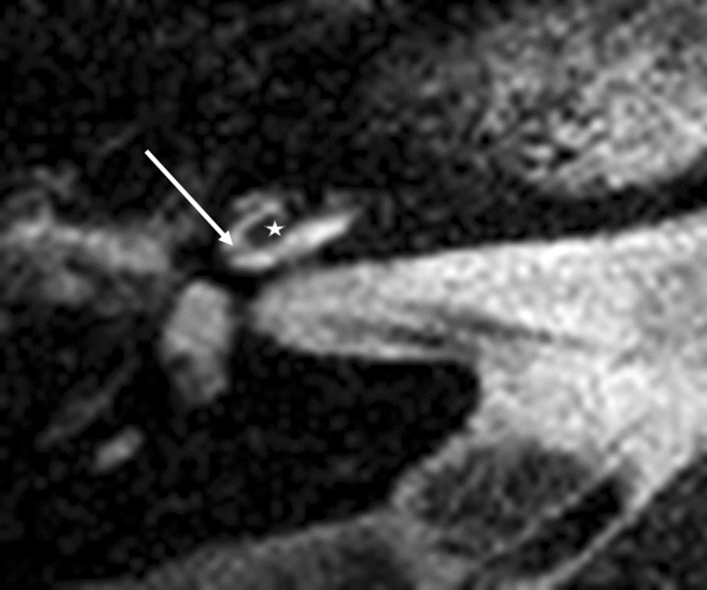

Figure 4.

Modiolar electrode, first turn, HFMS ST Position. Star represents diminishing electrode signal, arrow represents basilar membrane.

At the first turn, the estimation of the electrode position depends on the estimation of the basilar membrane and the diminishing localisation of the T2 signal by the electrode. In Fig. 5, diminishing occurred above the T2 signal and the basilar membrane signal, indicating fluid. This indicated the pattern of an electrode translocated into the scala vestibuli. Figure 7 of the same patient (No.10) confirms the irregular high position of the electrode in the first turn. In Figs. 3 and 4, the signal diminished above the electrode and the basilar membrane, indicating an electrode position in the scala tympani. Figure 6a and b are exemplary DVT of regular electrode positions at the floor of the basal and the first turn.

Modiolar electrode, first turn, HFMS SV Position. Star represents diminishing electrode signal, arrow represents basilar membrane. Pat.No.10.